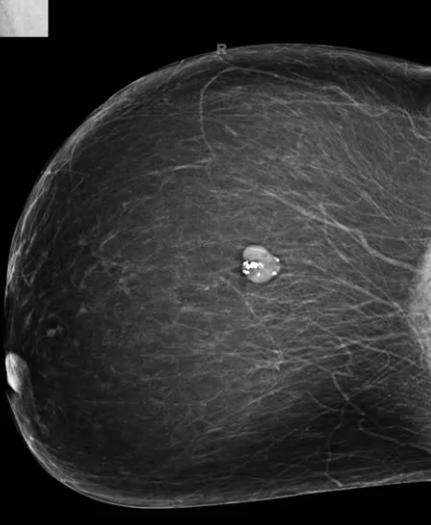

What is this an image of?

Benign mass